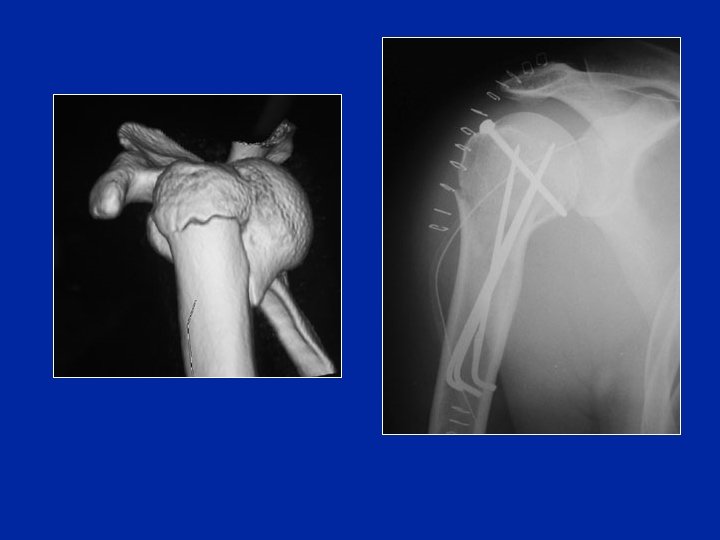

Fractures-luxations

Un cycliste tombe violemment sur le moignon de l’épaule. Il est très pâle mais conscient. C’est la première fois qu’il a un traumatisme de l’épaule. L’épaule est douloureuse et il est incapable de la mobiliser. Le membre supérieur est bloqué en abduction et rotation externe. A l’arrivée à l’hôpital l’épaule est tuméfiée et l’hématome qui est important gène l’examen clinique. La mobilisation passive de l’épaule est très douloureuse. Il existe une insensibilité du moignon de l’épaule. Les pouls périphériques sont perçus. Q 4 Quelle est votre conduite thérapeutique ? 1/ Si la radio ne montre pas de fracture du col huméral Réduction de la luxation (soit tentative de réduction lente, soit réduction sous AG) radio de contrôle 2/ Si la radio montre une fracture du col huméral Hospitalisation, bilan préop Réduction chirurgicale et ostéosynthèse de la fracture (plaque vissée ou clous élastiques) Immobilisation attelle 3 semaines puis mobilisation douce

Un cycliste tombe violemment sur le moignon de l’épaule. Il est très pâle mais conscient. C’est la première fois qu’il a un traumatisme de l’épaule. L’épaule est douloureuse et il est incapable de la mobiliser. Le membre supérieur est bloqué en abduction et rotation externe. A l’arrivée à l’hôpital l’épaule est tuméfiée et l’hématome qui est important gêne l’examen clinique. La mobilisation passive de l’épaule est très douloureuse. Il existe une insensibilité du moignon de l’épaule. Les pouls périphériques sont perçus. Q 5 Vous le traitez et pourtant son épaule devient raide et douloureuse dans les semaines suivantes, de même que son poignet alors que le moignon de l’épaule est redevenu sensible et non atrophié. Quelle complication secondaire vous évoque ce tableau ? Syndrôme épaule-main: algodystrophie du membre supérieur Phase chaude (pas de troubles trophiques)